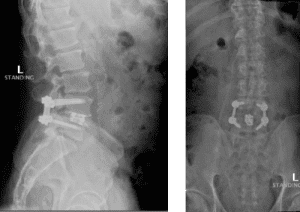

The grade 1 spondylolisthesis at L4/L5 requires both decompression at the L4/L5 level but also fusion because of the instability with motions. Here are three standing x-rays: one in the neutral position, one in flexion, and one in extensions. Notice the movement in the vertebral bodies at L4 and L5. This is abnormal motion and it can contribute to back pain and increase stenosis in certain positions. Thus, it requires decompression and stabilization with fusions.

Image 2. This shows the lumbar spine in motion. Notice the L4 and L5 level changes with flexion and extension. Notice the L2 and L3 levels do not have that type of motion. This is instability.